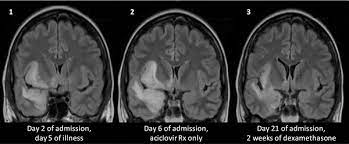

Herpes simplex virus (hsv) encephalitis hsv encephalitis (hsve) is the most common cause of infectious encephalitis (1); Initially clinical and brain mri findings were in favor of herpes simplex virus (hsv) encephalitis. The laboratory diagnosis of autoimmune encephalitis. Acute hsv encephalitis who had neuroimaging repeated within four weeks of the first scan. • occurs despite blood brain barrier with tight junctions.

The laboratory diagnosis of autoimmune encephalitis. The study analysed serially acquired magnetic resonance images (mri), of patients with acute hsv encephalitis who had neuroimaging repeated within four weeks of the first scan. Associated with hsv encephalitis (strong evidence). Its symptoms are fever, confusion, coma, and seizures. A case of granulomatous hsv encephalitis: Having said that, mri with contrast is considered the most sensitive imaging modality, and findings are present in over half of individuals 8. Severe infection, particularly untreated herpes simplex virus (hsv) encephalitis, can cause brain hemorrhagic necrosis. Herpes simplex encephalitis occurs as 2 distinct entities:

It is a severe condition brain mri may show limbic encephalitis (55) or diffuse t2 and dwi hyperintensities in the white matter, associated with restricted diffusion (54). Brain mri—increased t2 signal intensity in frontotemporal region → viral (hsv) encephalitis. Associated with hsv encephalitis (strong evidence). Provided cranial imaging has excluded any contraindications such as a space occupying lesion or severe cerebral oedema and brain shift, a csf. Having said that, mri with contrast is considered the most sensitive imaging modality, and findings are present in over half of individuals 8. In addition, because of the involvement of the. We performed volumetric measurements of the left and right temporal lobes and of cerebral oedema. Herpes simplex encephalitis occurs as 2 distinct entities: The study analysed serially acquired magnetic resonance images (mri), of patients with acute hsv encephalitis who had neuroimaging repeated within four weeks of the first scan. Pregnancy the most common cause of encephalitis in newborns is vaginal delivery from a mother who is infected with herpes simplex virus 2 (hsv 2). There is no particular age, sex, or seasonal predilection. Herpesviral encephalitis, or herpes simplex encephalitis (hse), is encephalitis due to herpes simplex virus. Severe infection, particularly untreated herpes simplex virus (hsv) encephalitis, can cause brain hemorrhagic necrosis.